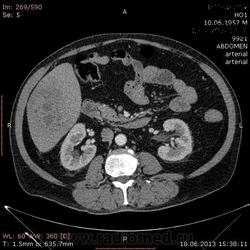

- https://radiomed.ru/sites/default/files/styles/case_slider_image/public/user/17529/img-0006-00001_2.jpg?itok=dK7FkYd5

На абсцесс похоже

На мой взгляд, абсцесс.

Тоже за абсцесс.

Cпасибо , коллеги.Сегодня больного прооперировали диагноз абсцесс правой доли печени.Оказывается больной когда - то получил тупую травму живота, об этом нам не говорил.....